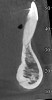

Fig 5. CBCT sagittal view of the same patient showing thin/no bone on the lingual aspect.

Figure 5

In cases with thin lingual bone, as measured on CBCT (<2.5 mm at a level of 8 mm apical to the CEJ), orthodontic treatment is not advisable, leaving surgical root coverage as the only option. However, the prognosis for this procedure is poorer, because the predominant cause is not addressed. Figure 4 shows the frontal clinical view of a patient with a hyperdivergent growth pattern who presented with post-orthodontic GR of a labially displaced lower central incisor. The sagittal CBCT view (Figure 5) shows complete absence of lingual bone, which contraindicated orthodontic tooth repositioning.